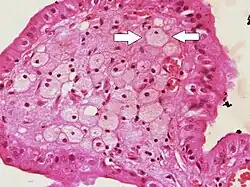

![]() |

Osteochondroma | Perichondrium covering the cartilage cap, which merged into the underlying spongiosa. | Category: Histopathology of osteochondroma | osteochondroma |